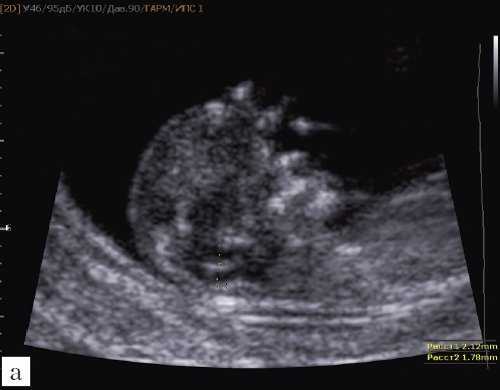

Ультразвуковая анатомия среднесагиттального скана головного мозга плода

Одним из критериев среднесагиттального корректного скана головного мозга плода в срок 11-14 недель беременности является отсутствие визуализации сосудистого сплетения и скуловой кости верхней челюсти, наличие визуализации кости носа и небного отростка верхней челюсти (рис. 1). Обязательным является наличие на скане диэнцефалона-таламуса (Thalamus), который продолжается в ствол мозга (brain stem), а также чуть ниже в средний мозг (midbrain), с продолжением в интракраниальное пространство, представляющее собой IV желудочек мозга, в котором можно визуализировать гиперэхогенное сосудистое сплетение. Между стенкой IV желудочка и затылочной костью видна анэхогенная большая цистерна головного мозга (cisterna magna). Между затылочной костью и кожей визуализируется воротниковое пространство. Для полноценной оценки структур среднего и заднего мозга необходимо оценить их наличие, размер, взаимоотношение, так как при патологии головного мозга и позвоночника эти критерии меняются.

Рис. 1. Ультразвуковая соноэмбриология структур головного мозга в среднесагиттальном скане в 13 недель беременности.

1 - диэнцефалон;

2 - средний мозг;

3 - ствол мозга;

4 - интракраниальное пространство, или IV желудочек;

5 - большая цистерна;

6 - воротниковое пространство.

Особенностями визуализации этих структур является их гипо/анэхогенность. Так, при сроках 11-14 недель беременности таламус, ствол мозга, средний мозг выглядят практически анэхогенными. Итак, нормальная ультразвуковая анатомия этих структур головного мозга плода имеет следующие особенности: ствол и IV желудочек выглядят как анэхогенные продолговатые структуры, имеющие непосредственную близость (как бы выходящие) из диэнцефалона и среднего мозга. Все выше перечисленные анатомические структуры могут быть измерены и должно быть оценено их взаиморасположение (рис. 2, а).

а) На эхограмме:

1 - ствол мозга;

2 - интракраниальное пространство, или IV желудочек;

3 - большая цистерна головного мозга;

4 - воротниковое пространство.

б) Вид "осьминожки":

- красный цвет - диэнцефалон (таламус), со стволом мозга (верхняя ножка) и IV желудочком (нижняя ножка);

- желтый цвет - большая цистерна головного мозга;

- синий цвет - воротниковое пространство.

Новый ультразвуковой маркер в изучении нормальной ультразвуковой анатомии головного мозга плода в срок 11-14 недель беременности

Особенности визуализации изложенных выше структур в данном сроке позволили нам выделить и назвать новый ультразвуковой маркер нормальной ультразвуковой анатомии мозга плода. Структуры головного мозга плода в этой области схожи с осьминогом, у которого есть голова и две приблизительно равновеликие по диаметру ножки, представляющие собой ствол мозга и IV желудочек. Ниже ножек "осьминожки" визуализируется 2 "подушки осьминожки" - это два анэхогенных пространства - большая цистерна и воротниковое пространство (рис. 2, б).

Так как речь идет о сроках первого скрининга, т.е. раннего осмотра, новый ультразвуковой маркер мы назвали "осьминожкой" (рис. 3).

а) Стрелками указана голова "осьминожки" - диэнцефалон (таламус).

б) Красный цвет - диэнцефалон (таламус), со стволом мозга (верхняя ножка) и IV желудочком (нижняя ножка); желтый цвет - большая цистерна головного мозга; синий цвет - воротниковое пространство.

Как сказано выше, имеет значение и измерение ножек "осьминожки", так среднее значение диаметра нижней ножки, т.е. IV желудочка в зависимости от КТР в срок 11-14 недель варьирует от 1,5 до 2,5 мм (рис. 4).

Рис. 4. Измерение и взаимоотношение ножек "осьминожки" - ствола мозга и IV желудочка у плода, беременность 12 недель.

Измерение ножек "осьминожки".

Красный цвет - диэнцефалон (таламус), со стволом мозга (верхняя ножка) и IV желудочком (нижняя ножка); желтый цвет - большая цистерна головного мозга; синий цвет - воротниковое пространство.